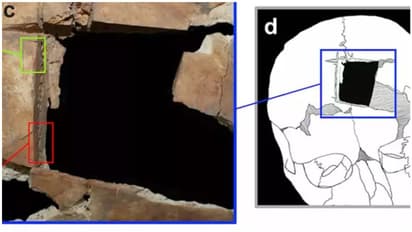

ഇസ്രായേലിലെ ടെൽ മെഗിദ്ദോയിലെ ഒരു ശവകുടീരത്തില് പുരാവസ്തു ഗവേഷകര് നടത്തിയ ഉത്ഖനനത്തിനിടെയാണ് മസ്തിഷ്കം തുറന്ന് ചികിത്സ നടത്തിയ ഒരു മനുഷ്യന്റെ അസ്ഥികൂടം പരുവസ്തു ശാസ്ത്രജ്ഞര്ക്ക് ലഭിച്ചത്. 1550 ബിസിയ്ക്കും 1450 ബിസിയ്ക്കും ഇടയിൽ ജീവിച്ചിരുന്ന വെങ്കലയുഗത്തിലെ സഹോദരന്മാരുടെ അസ്ഥികൂടമാണ് ഗവേഷകർ കണ്ടെത്തിയത്. ഇത് സംബന്ധിച്ച പഠനം പ്ളോസ് വണ് എന്ന ശാസ്ത്രീയ മാസികയില് പ്രസിദ്ധീകരിച്ചു. തലയോട്ടിയില് ദ്വാരമുണ്ടാക്കി ചികിത്സ നടത്തുന്നത് (Trephination) ചരിത്രപരമായി ലോകമെമ്പാടും നിലനിന്നിരുന്ന പുരാതന നാഗരികതകളില് ഒരു വൈദ്യസമ്പ്രദായമാണെന്ന് പഠനം പറയുന്നു. എന്നാല്, ഈ സമ്പ്രദായം വെങ്കലയുഗം മുതല് നിലനിന്നിരുന്നുവെന്നാണ് ഇപ്പോഴത്തെ പഠനം പറയുന്നത്.

ബിസി 19-ാം നൂറ്റാണ്ടിൽ ഈ മേഖലയിലെ ഏറ്റവും സമ്പന്നവും കോസ്മോപൊളിറ്റൻ നഗരവുമയിരുന്നു മെഗിദ്ദോയെന്ന് പഠനത്തിന്റെ സഹ-രചയിതാവ് ഇസ്രായേൽ ഫിങ്കൽസ്റ്റീൻ പറയുന്നു. ലഭിച്ച അസ്ഥികൂടങ്ങളില് നിന്ന് മൂത്ത സഹോദരന് 21 നും 46 നും ഇടയില് പ്രായമുണ്ടെന്ന് കണക്കാക്കുന്നു. ഇളയ സഹോദരനാകട്ടെ 20 കളുടെ തുടക്കത്തിലാണ്. ഇതില് മൂത്ത സഹോദരന്റെ തലയോട്ടിയിലാണ് ശസ്ത്രക്രിയ നടത്തിയതിന്റെ തെളിവുകള് ലഭിച്ചതെന്നും പഠനം ചൂണ്ടിക്കാട്ടുന്നു. ഈ സഹോദരങ്ങള് സമൂഹത്തിലെ ഉന്നതരോ രാജകീയ അംഗങ്ങളോ ആയിരിക്കാം. അങ്ങനെയാകാം അവര്ക്ക് അപൂർവമായ വൈദ്യചികിത്സ ലഭിച്ചതെന്നും ഗവേഷക സംഘത്തിലെ പ്രധാനിയായ റേച്ചല് കാലിഷര് പറഞ്ഞു.

മൂത്ത സഹോദരനില് നിന്ന് കുഷ്ഠരോഗത്തിന്റെ ലക്ഷണങ്ങളും കണ്ടെത്തി. ഇതുവരെ ലഭിച്ചതില് വച്ച് ഏറ്റവും പഴക്കം ചെന്ന കുഷ്ഠരോഗിയാണ് ഇദ്ദേഹം. ഇതോടെ കുഷ്ഠരോഗാണുക്കള് 3,500 വര്ഷങ്ങള്ക്ക് മുമ്പ് തന്നെ ഭൂമുഖത്ത് ഉണ്ടായിരുന്നതിന് തെളിവുകളാണ് ലഭിച്ചത്. ഇരുവരും അവരുടെ ജീവിതകാലത്ത് ഗുരുതരമായ രോഗബാധിതരായിരുന്നിരിക്കാം. എന്നാല് അവരുടെ ഏത് രോഗത്തിനാണ് തലയോട്ടി തുറന്ന് ചികിത്സിച്ചതെന്ന് വ്യക്തമല്ല. ചിലപ്പോള് ശസ്ത്രക്രിയയ്ക്ക് പിന്നാലെ രോഗി മരിച്ചിരിക്കാം. ഏങ്കിലും പുരാതനകാലത്ത് തന്നെ മനുഷ്യന് തലയോട്ടി തുറന്ന് ചികിത്സ നടത്താന് ശ്രമിച്ചിരുന്നെന്നത് വൈദ്യശാസ്ത്ര രംഗത്തെ വളര്ച്ചയെ കാണിക്കുന്നെന്ന് റേച്ചല് കാലിഷര് പറഞ്ഞു. ലോകത്തിന്റെ വിവിധ സ്ഥലങ്ങളില് പുരാതന കാലത്ത് തന്നെ ട്രെഫിനേഷൻ ചികിത്സ നടന്നിരിക്കാന് സാധ്യതയുണ്ടെന്നും അദ്ദേഹം കൂട്ടിച്ചേര്ത്തു.